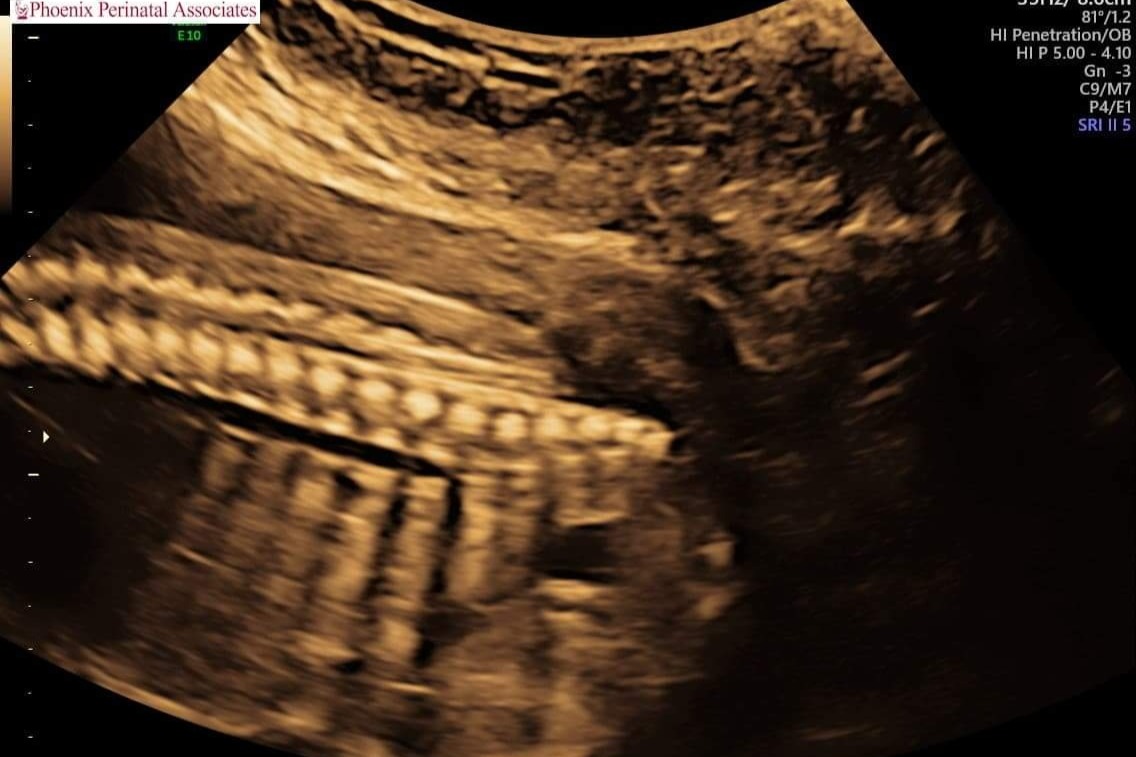

On Tuesday May 11th 2021 our family received fateful news that any expecting parent dreads hearing: our baby has a birth defect. Spina bifida myelomeningocele, a rare neural tube defect that causes baby's spine to not fuse properly which results in their spinal cord, nerves, and spinal fluid to pool outside of the spinal column. Common issues with this include paralysis, ambulatory, and developmental difficulties.